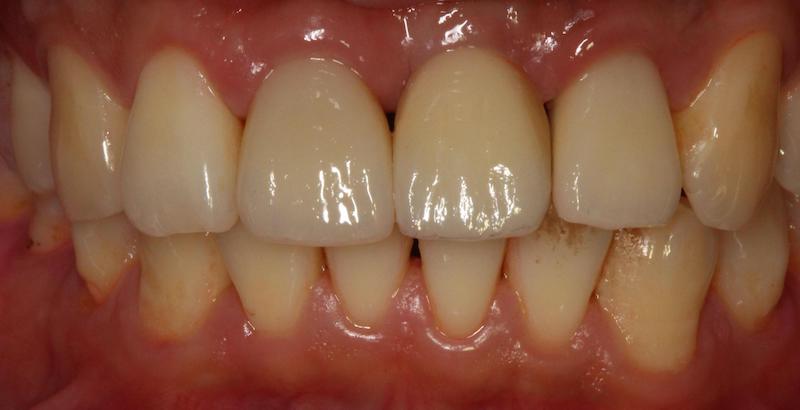

最終,我們以三顆全瓷冠假牙修復完成。我們確實也達到我們所設定的目標:在牙齒的顏色、長度寬度、牙齒之間和牙齦高度的協調性都很高。也相信 Mr.Wang 有了兼具功能、美觀的牙齒,一定更能展現充滿自信的笑容。

完成人工植牙後,與桃園全瓷美學專家沈志容醫師合作,以數位全瓷冠修復三顆前牙 完成的全瓷冠牙套顏色、細節逼真,前牙咬合時幾乎看不出差異